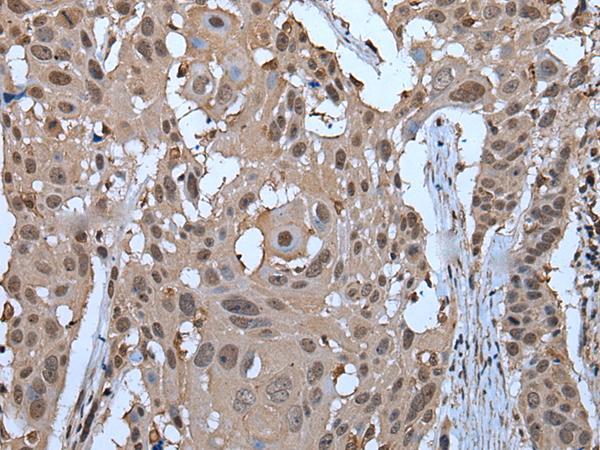

- Submitted by

- LSBio (provider)

- Enhanced method

- Genetic validation

- Main image

- Experimental details

- Immunohistochemistry of paraffin-embedded Human esophagus cancer tissue using ZNF787 Polyclonal Antibody at dilution of 1:45(×200)